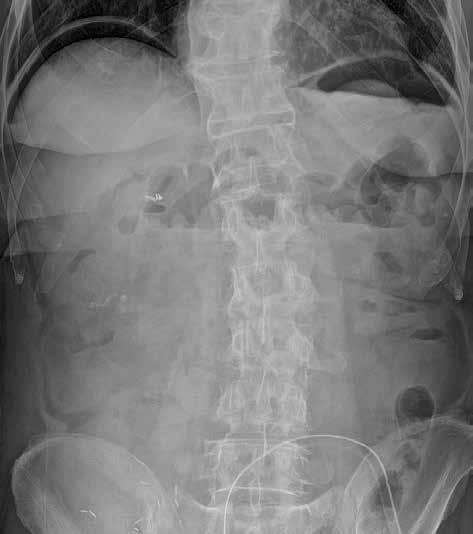

Snímek břicha horizontálním paprskem vestoje se provádí s cílem zobrazit hladinky a volný vzduch v dutině břišní. Jako hladinky označujeme tzv. hydroérický fenomén neboli rozhraní mezi tekutinou a plynem v lumen střeva (obr. 3). Fyziologicky obsahuje tenké střevo cca 200 ml vzduchu a 2000 ml tekutiny, která však stále cirkuluje. Hladinky, které se na hranici tekutina/plyn ve střevních kličkách tvoří, můžeme zachytit i u zdravého jedince, u pacientů s malasimilačním syndromem a u nemocných s paralytickým ileem. Nejčastěji se s hladinkami setkáváme u nemocných s mechanickou překážkou střevní průchodnosti. Někdy lze podle lokalizace a tvaru hladinek odhadnout místo a příčinu poruchy střevní pasáže. Při akumulaci tekutiny a vzduchu v lumen střeva dochází k jeho dilataci na 3,5–4 cm (někdy až 5 cm i více). K distenzi trávicí trubice dochází orálně od místa obstrukce.

Obr. 2, 3: RTG snímek břicha vleže a vestoje. Ileus tenkého střeva. Vleže je dobře patrná dilatace kliček tenkého střeva nad 3 cm (2). Tenké střevo odlišíme od tlustého přítomností plicae circulares, které obkružují celý obvod lumen střeva. Vstoje vidíme v tenkém střevě hladinky (3).